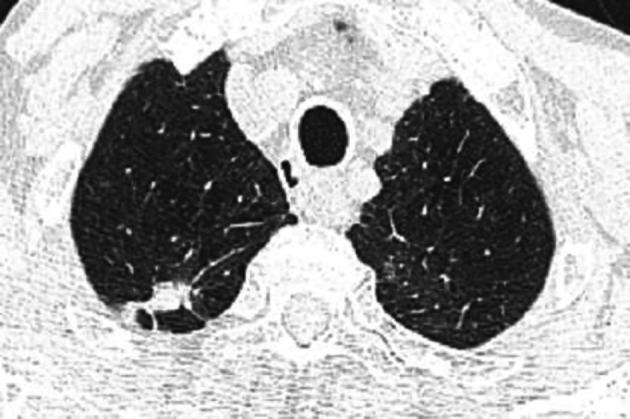

Idiopathic pleuroparenchymal fibroelastosis (IPPFE) is a very rare and a slowly conspicuous progressing chronic lung disease, which usually involves the upper lobes of the lung. This unusual disease, first recognized as a rare idiopathic interstitial pneumonia in 2013, is characterized by dense fibrosis of the visceral pleura and the subjacent lung parenchyma accompanied by elastosis predominating in the subpleural alveolar walls. In the interest of improving our understanding of this uncommon disease, we report a case of IPPFE established by pathology results. A 73-year-old male patient, smoker, with a medical history of chronic obstructive pulmonary disease, presented since January 2022 with a gradual worsening of dyspnea on exertion and productive cough with weight loss. The chest X-ray detected a thoracic distention. The chest high resolution computed tomography revealed biapical subpleural parenchymatous condensations with tractive bronchiectasis and pleural retraction in the right upper lobe and diffuse bilateral cento-lobular emphysema. A scan-guided trans-parietal lung biopsy showed lung parenchyma tattooed with anthracosic deposits, largely remodeled by fibrous tissue, intermingled with numerous wavy and refractive dyselastotic structures in polarized light. The orcein staining confirmed the presence of excess elastosic fibers within these lesions. All etiological investigations were negative. His lung function studies revealed a reversible obstructive ventilatory disorder. Following a multidisciplinary discussion, the diagnosis of IPPFE was confirmed on the basis of the distribution in the upper lungs on chest computed tomography combined with pathology pattern. This case emphasizes the atypical misleading radiological presentation of IPPFE and the key role of pathological results in establishing the diagnosis. Hence, further studies are needed to improve our understanding of this uncommon disease and to establish clear-cut guidelines for IPPFE diagnosis and management.

特发性胸膜肺弹力纤维增生症(IPPFE)是一种非常罕见且进展缓慢的慢性肺部疾病,通常累及肺部上叶。这种不常见的疾病于 2013 年首次被认为是一种罕见的特发性间质性肺炎,其特征为脏层胸膜和下肺部实质的致密纤维化,伴弹性组织增生为主的亚胸膜肺泡壁。为了提高对这种罕见疾病的认识,我们报告了一例经病理证实的 IPPFE 病例。一名 73 岁男性患者,吸烟者,有慢性阻塞性肺疾病病史,自 2022 年 1 月以来,逐渐出现劳力性呼吸困难加重和咳痰伴体重减轻。胸部 X 线检查发现胸部膨胀。胸部高分辨率计算机断层扫描显示右上叶双肺尖下胸膜实质混浊,伴有牵引性支气管扩张和胸膜回缩,以及双侧弥漫性中心小叶性肺气肿。经皮肺活检显示肺实质有炭末沉着,大部分被纤维组织重塑,在偏光下可见许多波浪状和折射性弹性不良结构。奥辛染色证实这些病变中存在过多的弹性纤维。所有病因学调查均为阴性。他的肺功能研究显示存在可复性阻塞性通气障碍。经过多学科讨论,根据胸部 CT 检查中肺部上叶的分布和病理模式,确诊为 IPPFE。 该病例强调了 IPPFE 不典型的误导性放射学表现以及病理结果在确立诊断中的关键作用。因此,需要进一步研究以提高对这种罕见疾病的认识,并为 IPPFE 的诊断和管理制定明确的指南。